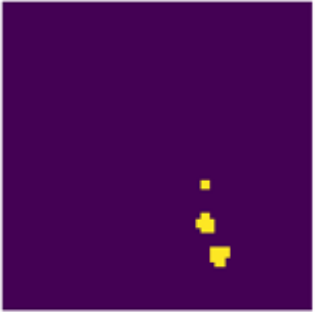

Disentangled PET Lesion Segmentation

Tanya Gatsak, Kumar Abhishek, Hanene Ben Yedder, Saeid Asgari Taghanaki, Ghassan Hamarneh

International Symposium on Biomedical Imaging (IEEE ISBI), 2025

(Best Paper Award)

We present a 3D disentanglement method for PET lesion segmentation that separates disease and healthy anatomical features and employs losses for segmentation, reconstruction, and healthy component plausibility. [Abstract] [BibTeX] [Presentation Slides]

PET imaging is an invaluable tool in clinical settings as it captures the functional activity of both healthy anatomy and cancerous lesions. Developing automatic lesion segmentation methods for PET images is crucial since manual lesion segmentation is laborious and prone to inter- and intra-observer variability. We propose PET-Disentangler, a 3D disentanglement method that uses a 3D UNet-like encoder-decoder architecture to disentangle disease and normal healthy anatomical features with losses for segmentation, reconstruction, and healthy component plausibility. A critic network is used to encourage the healthy latent features to match the distribution of healthy samples and thus encourages these features to not contain any lesion-related features. Our quantitative results show that PET-Disentangler is less prone to incorrectly declaring healthy and high tracer uptake regions as cancerous lesions, since such uptake pattern would be assigned to the disentangled healthy component. Our code is available on GitHub.